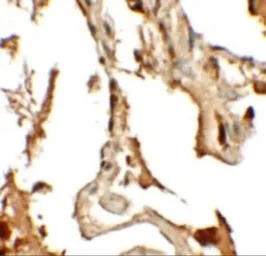

IHC-P analysis of human lung tissue using GTX31848 RILPL2 antibody.

Working concentration : 2.5 μg/ml